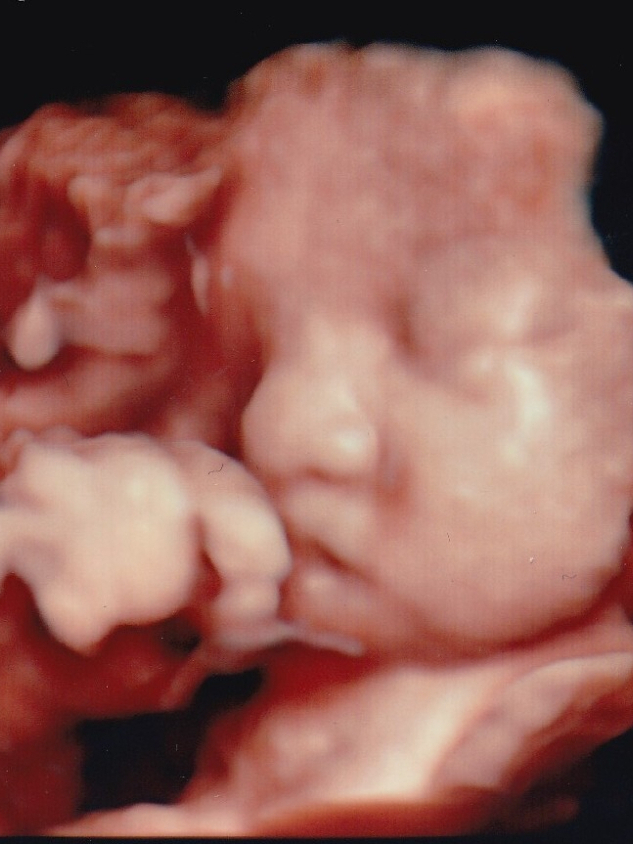

妊婦健診時の赤ちゃんの超音波画像記録について(ベビー動画館)

ご希望の方には「ベビー動画館」アプリをご利用いただき、お一人様ごと専用IDにてスマートフォンからいつでも健診動画をみることができます。